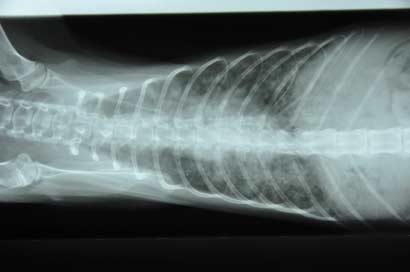

Die Röntgenbilder zeigen einen deutlich veränderten Lungenbereich, was gut zu einer Bronchopneumonie passen würde. Die Klinik schlägt jedoch vor, noch abzuklären, ob evtl. Parasiten sprich Lungenwürmer involviert sind.

Unser - gerade mal 1,6 kg schweres - Leichtgewicht musste vorsorglich in die Tierklinik zum Check eingeliefert werden. Die Untersuchungen sind noch nicht komplett abgeschlossen, aber anhand der Röntgenbilder konnte schon eine starke Lungenentzündung diagnostiziert werden. Lili musste sofort medizinisch versorgt werden, es war höchste Zeit.